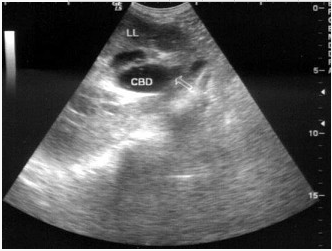

患者女53岁,上腹部疼痛不适半年余,皮肤、巩膜黄染进行性加重。B超检查如图所示,根据超声声像图诊断为()。

A:胆总管下段癌

B:胰头癌

C:胆总管炎性狭窄

D:胆总管结石

E:胆总管蛔虫